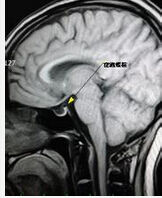

診斷ESS除注意上述臨床表現外關鍵是確定空蝶鞍的存在,即鞍上池蛛網膜下腔進入鞍內且垂體受壓。影像學檢查是診斷的主要方法,包括蝶鞍平片、CT和MRI,平片只能發現蝶鞍擴大等間接徵象不易與垂體瘤鑑別,氣腦造影可發現氣體進入鞍內以資鑑別,X線平片結合氣腦造影曾是空蝶鞍綜合徵的主要診斷方法:可見蝶鞍擴大呈球形或方形,骨質疏鬆、造影時氣體可進入鞍內。目前CT及MRI為診斷空蝶鞍綜合徵的可靠方法,尤其是MRI診斷準確率最高,其可清晰顯示垂體受壓變薄、向後下方移位,主要表現為:1.蝶鞍擴大或正常、鞍內充填大量腦脊液,呈明顯長T1長T2信號。2.垂體受壓變扁、厚度≤3mm,緊貼鞍底、矢狀位呈短弧線狀,冠狀位呈向下淺弧形成“錨狀”冠狀位上垂體柄居中,矢狀位上可見其後移。CT冠狀薄層掃描可以觀察到垂體組織並避免骨偽影干擾。